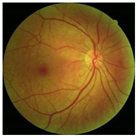

Figure 4.

Example of DDR dataset: (a) normal; (b) NPDR; (c) PDR.

In this study, we used the Dataset for Diabetic Retinopathy (DDR) dataset [13], one of the fundus image datasets that became available to the public in 2019. This relatively new dataset contains 13,673 fundus images from 9598 patients collected from several hospitals in China in 2016–2018. DDR fundus images were collected from several different camera types using single-view and captured using the same technique. It consists of six categories, such as normal (6266 data), mild NPDR (630 data), moderate NPDR (4477 data), severe NPDR (236 data), PDR (913 data), and the undegradable images with poor quality (1151 data). It should be noted that classes are very unbalanced in the DDR datasets. The classification of unbalanced classes is challenging due to the highly skewed distribution of classes and the unequal costs of misclassification. Li, Gao, Wang, Guo, Liu, and Kang [13] state that lesions on the fundus image of mild NPDR are difficult to identify, and some severe NPDR classes are also easily misclassified as moderate NPDR. Therefore, we balanced this dataset by re-sampling using only three classes: normal, NPDR (mild, moderate, and severe classes were combined into one class), and PDR. Then, each class contains 913 data points, adjusting the amount of data in the PDR class with the distribution of training, validation, and testing data as described in Table 1. A sample of the DDR dataset is presented in Figure 4. It can be seen that there are no DR lesions on the normal retina. Retinal signs of NPDR can be observed in the presence of lesions, such as exudates, MAs, and HAs. Meanwhile, new blood vessels form in the retina affected by PDR (advanced DR cases).